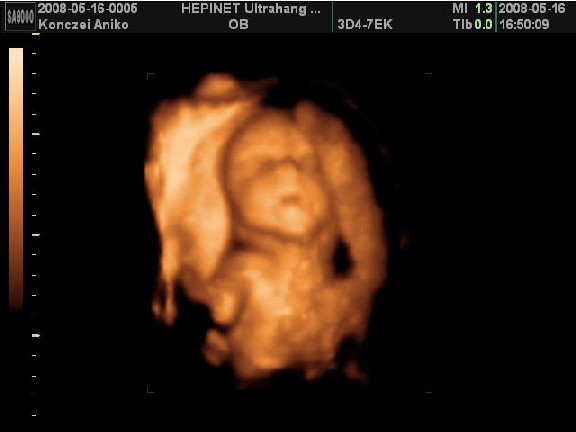

Voltam már uh-n 3x. Az elsőn 6 hetesen, mert barnáztam akkor 2 napig, majd 2 hét múlva is egy napig...A következő 10hetesen volt, mert már nem bírtam magammal, tudni akartam, h minden ok odabent. És végül a 12 hetes uh 12+3-on..ekkor minősítették 16+6-ra. A nemét még nem tudjuk, de nagyon kiscsajt szeretnék...hát majd kiderül. Most hétvégén majdnem elrohantam 4D-re, mert ismét nem bírok magammal...de szerencsére fullon voltak, meg a nő amúgyis le akart beszélni a 4D-ről, mondván csak 24hét után érdemes...szép. Így mostmár úgy döntöttem, hogy inkább kivárom a 3 hetet, amikoris hazalátogatok 5 napra. Jún. 5-én fogok elmenni 4D-re otthon, ahol kb 1/4-be kerül. Ja és nem fogjátok elhinni, de itt azért is külön fizetni kell, hogy a nemét megmondják.